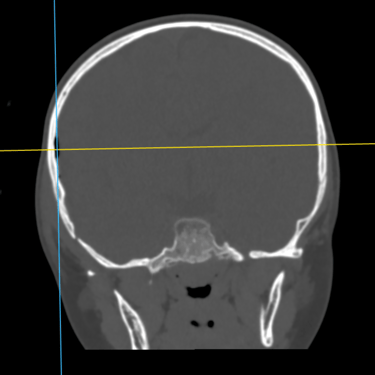

Fractura Craneal | Diagnóstico por Tomografía

La fractura craneal es una lesión que puede producirse tras un traumatismo craneoencefálico, con riesgo de comprometer el cerebro y las estructuras intracraneales. Los síntomas incluyen dolor local, edema, hematomas y, en casos graves, alteración del nivel de conciencia. La tomografía computarizada (TC) es el estudio de elección para su diagnóstico, ya que permite identificar con precisión el trazo de fractura, desplazamientos óseos, hemorragias asociadas y la afectación de senos venosos o base de cráneo. Un diagnóstico temprano mediante TC es esencial para definir la conducta terapéutica y prevenir complicaciones neurológicas potencialmente graves.